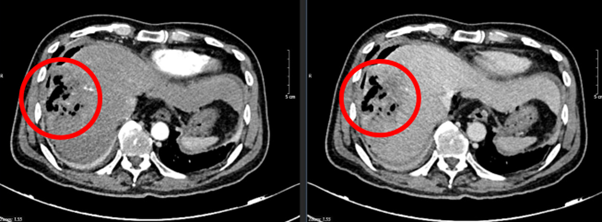

Hình 1: Hình ảnh chụp cắt lớp vi tính ổ bụng: Nhu mô hạ phân thùy S7-8 có khối (vòng tròn đỏ) tỷ trọng hỗn hợp kích thước 81x51mm gồm phần tăng tỷ trọng của vật liệu can thiệp và nhiều bóng khí tạo thành ổ tụ khí trong nhu mô kèm phần hoại tử dạng dịch, không có huyết khồi.

Các lần chụp cắt lớp vi tính ổ bụng cho thấy khối u gan giảm kích thước đáng kể, không còn tăng sinh mạch, không có huyết khối. Kích thước u giảm từ 81 x 51 mm ban đầu xuống còn khoảng 22 x 45 mm sau 20 chu kỳ điều trị.

Theo tiêu chuẩn RECIST 1.1, bệnh nhân đạt đáp ứng một phần (PR - Partial Response).